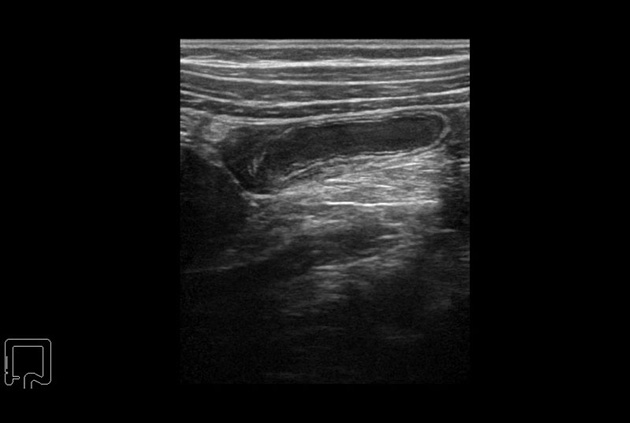

Panoramic View

Provides an extended field-of-view image created from a series of real-time images. As the user moves the transducer across the area of interest a larger image is created that provides clearer spatial relationship information of anatomy and structures. This is especially helpful in assessing structures that are larger than the transducer field of view.